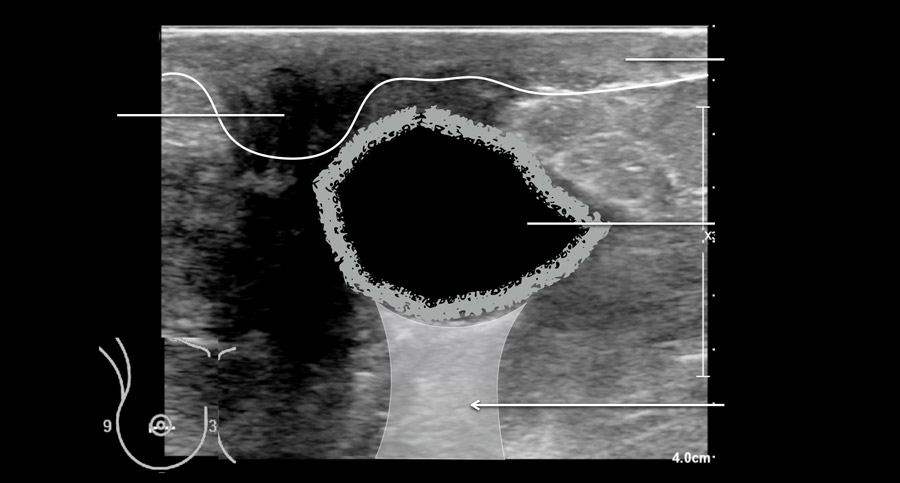

Đây là một ví dụ điển hình về nhiều nang ở một phụ nữ có khối u sờ thấy được ở vú.

Mặc dù có nhiều nang, nhưng chỉ có nang ở trung tâm mới sờ thấy được, vì nang này có hình tròn với dịch chịu áp lực căng bên trong.

Các nang còn lại không sờ thấy được, vì chúng có cảm giác tương tự như mô vú bình thường xung quanh.

Việc phát hiện thêm nhiều nang ở một phụ nữ đến khám vì có nang sờ thấy được là điều rất thường gặp.

Đây là video về một nang có thể sờ thấy được.

Trong trường hợp này, nang gây đau và được quyết định thực hiện chọc hút dịch.

Lưu ý rằng thành nang hơi dày.

Đây thường là dấu hiệu của nhiễm trùng độ thấp và giải thích tại sao nang gây đau.

Các nang không biến chứng thường không gây đau.

Đây là một nang nhiễm trùng khác, đã được chọc hút.

Chọc hút là một thủ thuật nhanh chóng và đơn giản.

Trong hầu hết các trường hợp, dịch hút ra có màu vàng trong suốt, nhưng cũng có thể có màu xanh lá hoặc nâu.

Không cần thiết phải xét nghiệm dịch hút ra.